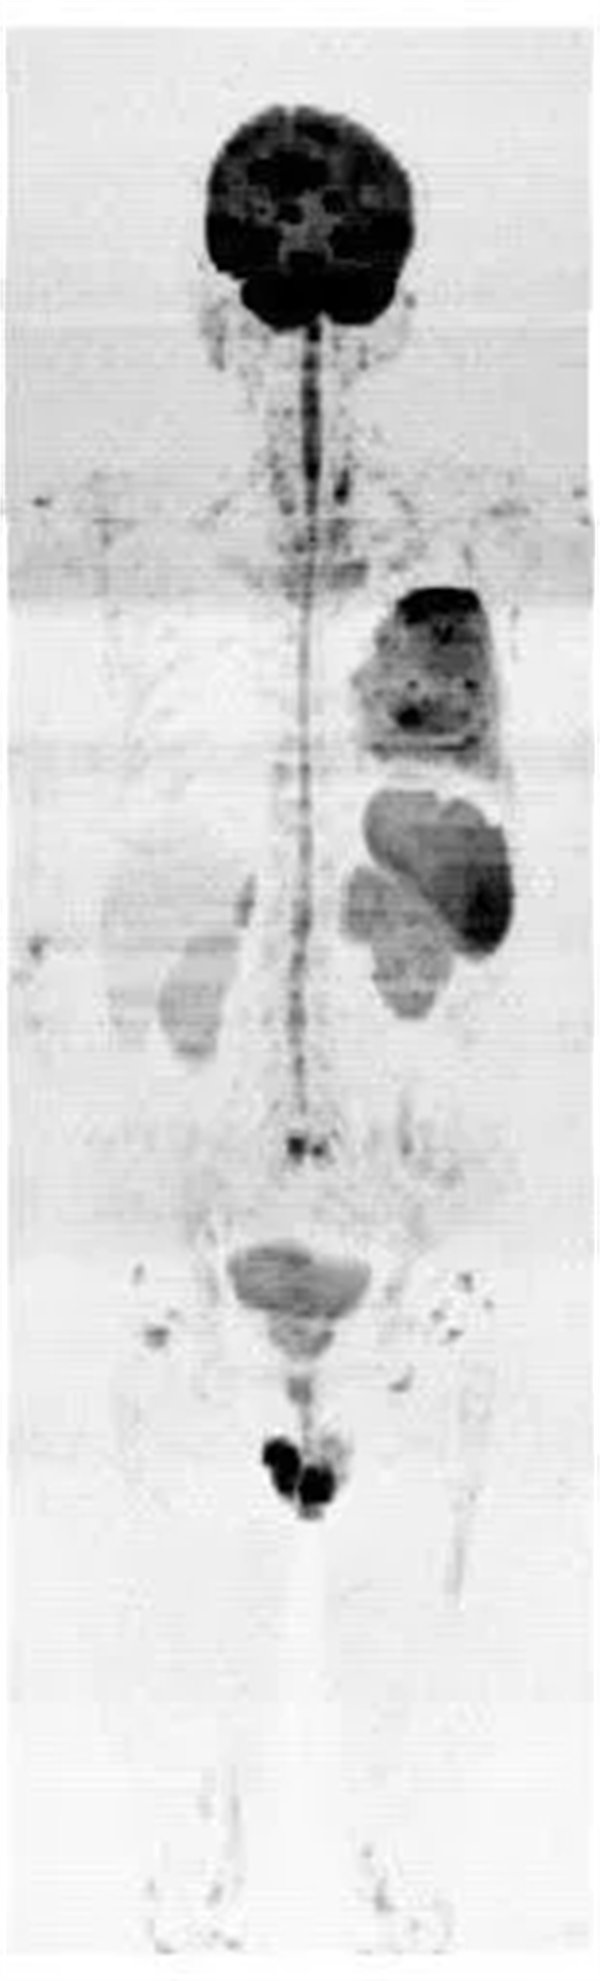

圖2:全身彌散成像反轉(zhuǎn)圖

磁共振全身彌散加權(quán)成像(WB-DWI),是將彌散加權(quán)成像技術(shù)與自動拼接技術(shù)和全景成像矩陣相結(jié)合而獲得全身的彌散加權(quán)成像影像。所得影像經(jīng)黑白翻轉(zhuǎn)后可達(dá)到與正電子發(fā)射計(jì)算機(jī)體層顯像(PET)影像類似的效果,故被稱為“類PET”,是近年來發(fā)展起來的全新影像檢查新技術(shù)。

該技術(shù)能夠進(jìn)行全身大范圍掃描,并加以3D后處理重建,可獲得全身腫瘤篩查、良惡性腫瘤的鑒別、腫瘤TNM分期及療效隨診等診斷信息,全身彌散技術(shù)把肌肉、脂肪、肝臟等組織背景信號抑制掉,突出了病變的顯示,大大提高了病變組織尤其是惡性腫瘤及其轉(zhuǎn)移灶的檢出率。